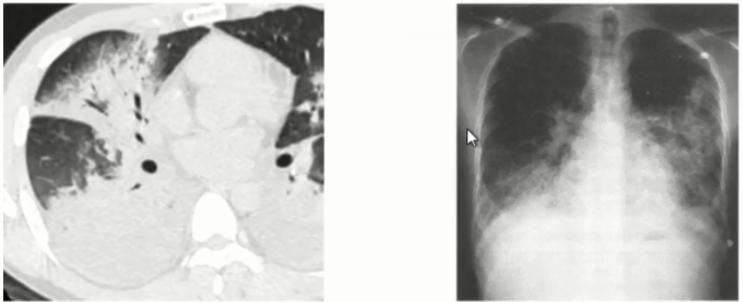

图1 患者的影像学以实变为主